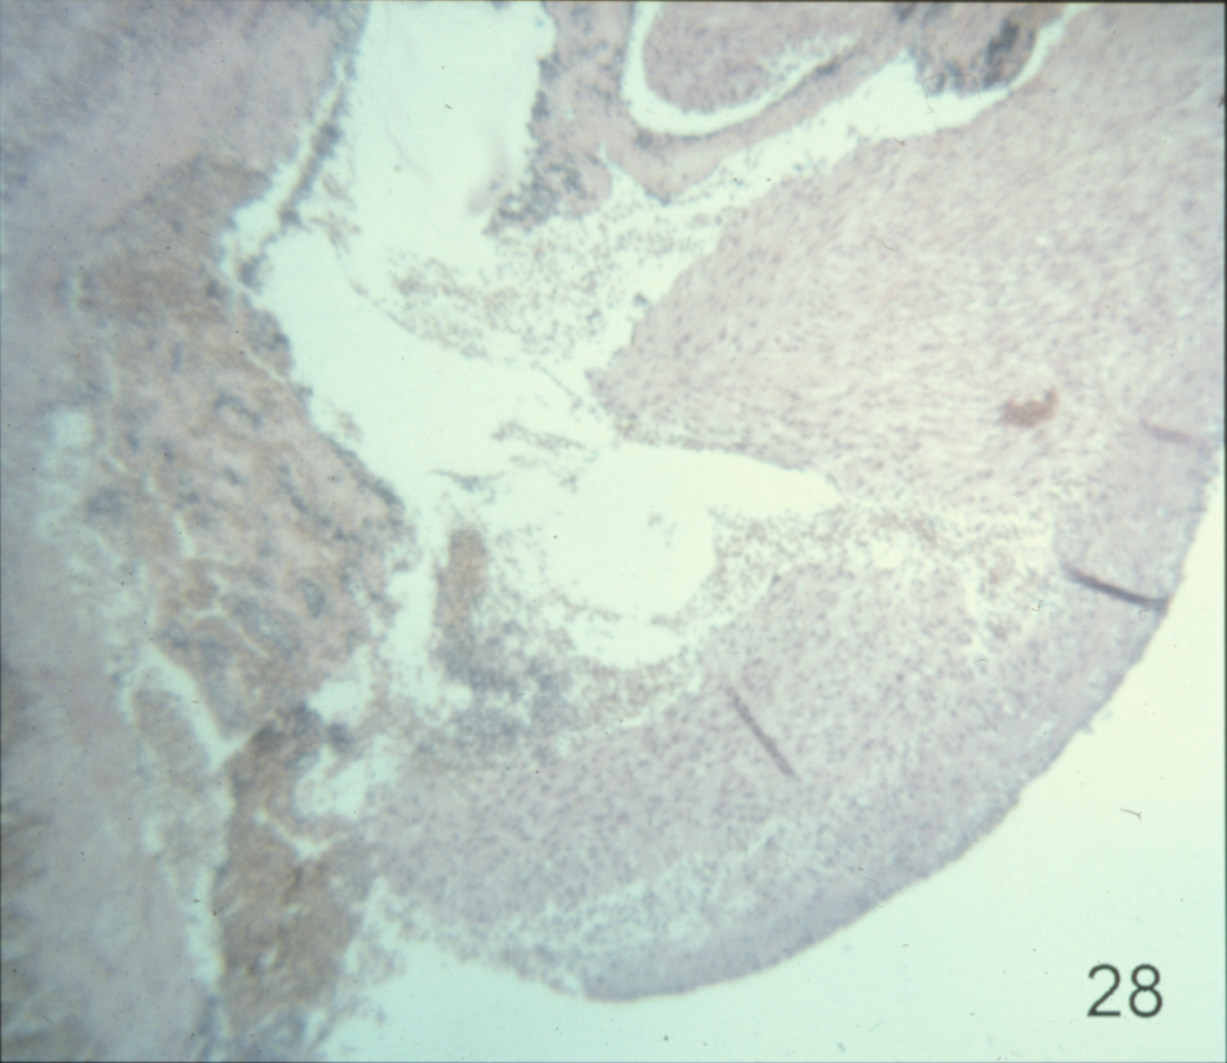

Cardiovascular disease in turkeys (slide study set no. 24) Item Info

Cardiovascular disease in turkeys (slide study set no. 24)

Turkeys--Diseases Cardiovascular system--Diseases

Slide Study Set #24, Cardiovascular Diseases in Turkeys (includes 27 color slides), 2001